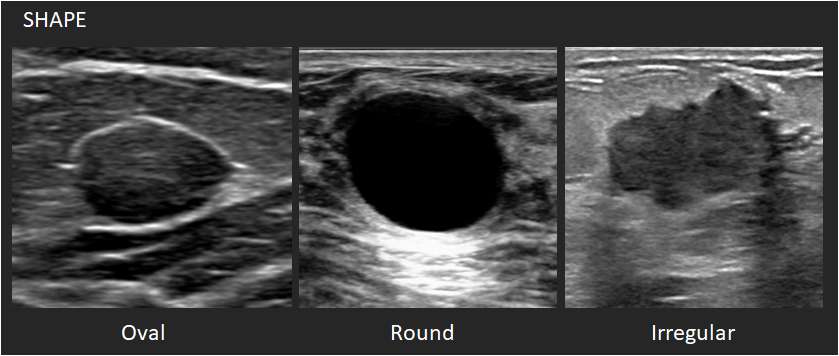

Shape:

1. Oval: This shape is elliptical or egg-shaped. An oval mass may include two or three undulations.

2. Round: This shape is spherical, ball-shaped, circular or globular.

3. Irregular: This shape is neither round nor oval.

Ultrasounds Mass Shapes